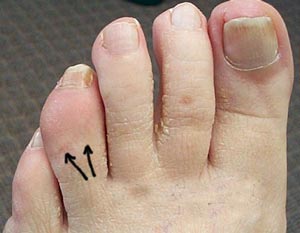

تغییر شکل پا، مانند انگشت چکشی یا پا چنبری، میتواند باعث درد کف پا شود. شرایط پزشکی مانند دیابت یا چاقی ممکن است باعث ایجاد استرسهای اضافی بر پا و درنتیجه درد کف پا شود.

ورم مفاصل پسوریاتیک حالت التهابی آرتروز مزمن است که باعث میشود انگشتان دست و پا متورم شوند و باعث درد یا سفتی رباطها و تاندونهای بدن، بهخصوص نقاطی که به استخوانهای پا متصل میشوند و همچنین مناطق دیگر بدن مانند قسمت توپی کف پا، میشود.